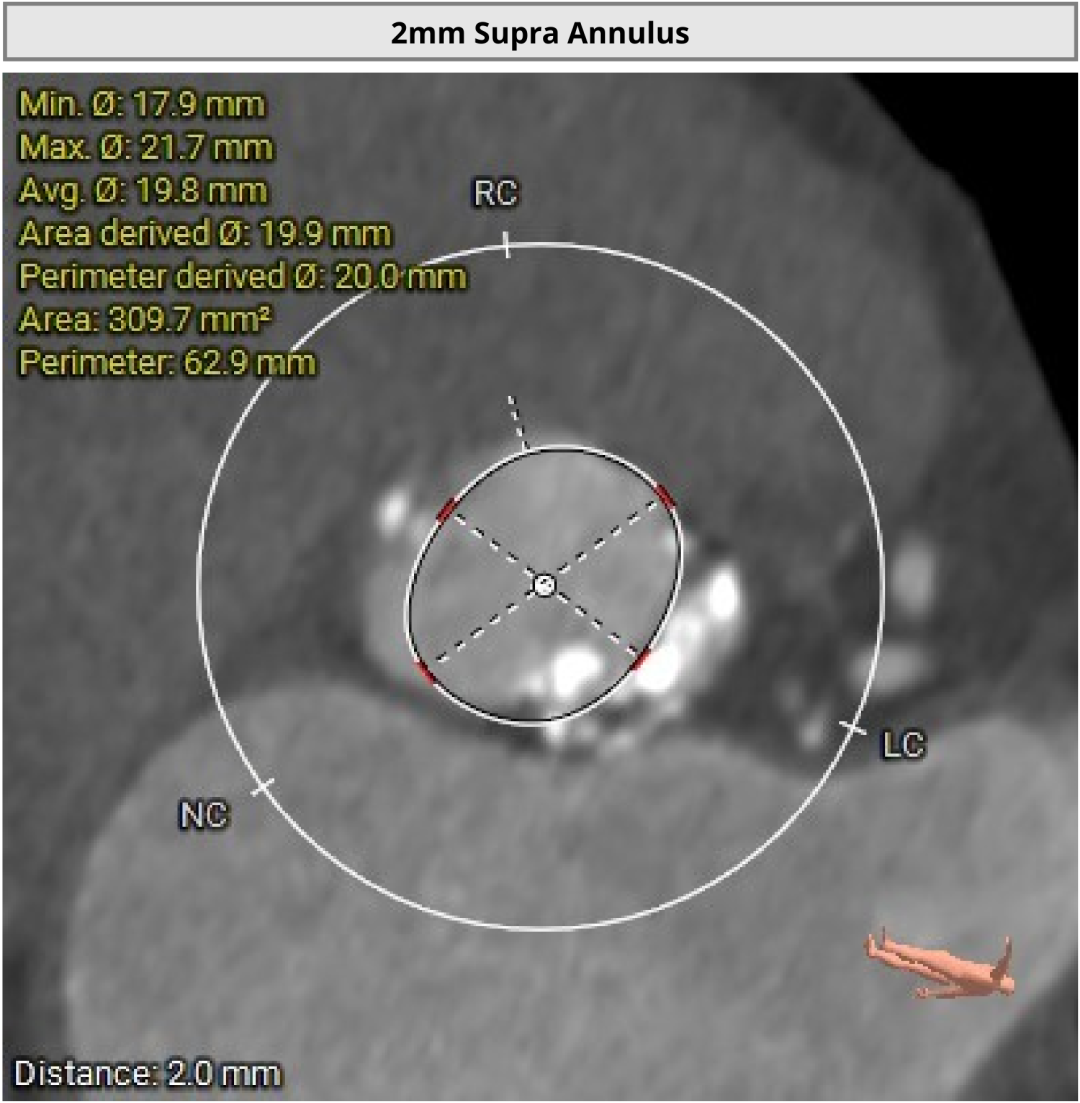

进一步检查显示,患者存在主动脉瓣重度狭窄并中度反流。超声心动图提示,主动脉瓣口面积约0.8cm²,同时伴有室壁节段性运动异常、左房及左室增大,左室收缩和舒张功能减退,左室射血分数为46%。此外,还可见二尖瓣轻度反流、三尖瓣轻至中度反流及轻度肺动脉高压。

术前CT评估显示,患者瓣膜解剖条件总体具备经导管治疗基础,双侧冠脉阻塞风险偏低。

进一步评估显示,患者瓣膜狭窄程度重,瓣叶钙化明显,左心室腔径偏小,手术中对器械通过、瓣膜释放以及循环稳定性的要求都更高。团队结合术前影像和整体身体状况,制定了周密的介入治疗方案,并做好相关风险预案。

CT评估

瓣膜评估